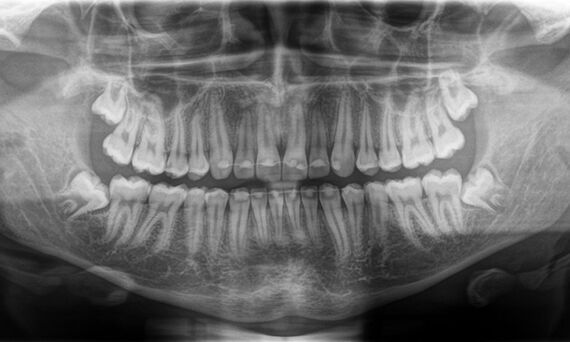

DCS converts X-rays directly into electrical signals, with no information loss. The DCS sensor creates razor-sharp, high-contrast panoramic X-ray images of exceptional quality.

Autofocus

The autofocus function delivers sharp, autofocused panoramic images even in anatomically difficult cases. This is all achieved with just the touch of a button and without additional intermediate steps.

Sharp Layer Technology

The jaw automatically lies in the sharp plane due to the individual and automatic adjustment to the patient's anatomy. A sharp panoramic image is then created from thousands of individual projections.

Direct Conversion Sensor (DCS): Sharp Image Details

The Direct Conversion Sensor (DCS) has revolutionized the standard of panoramic imaging. X-rays are directly converted into electrical signals. Thus, there is no signal loss due to light conversion as with conventional systems. The result: images with an extremely high and high-contrast level of sharpness - even at a very low dose. For clear diagnoses and even more targeted treatment.